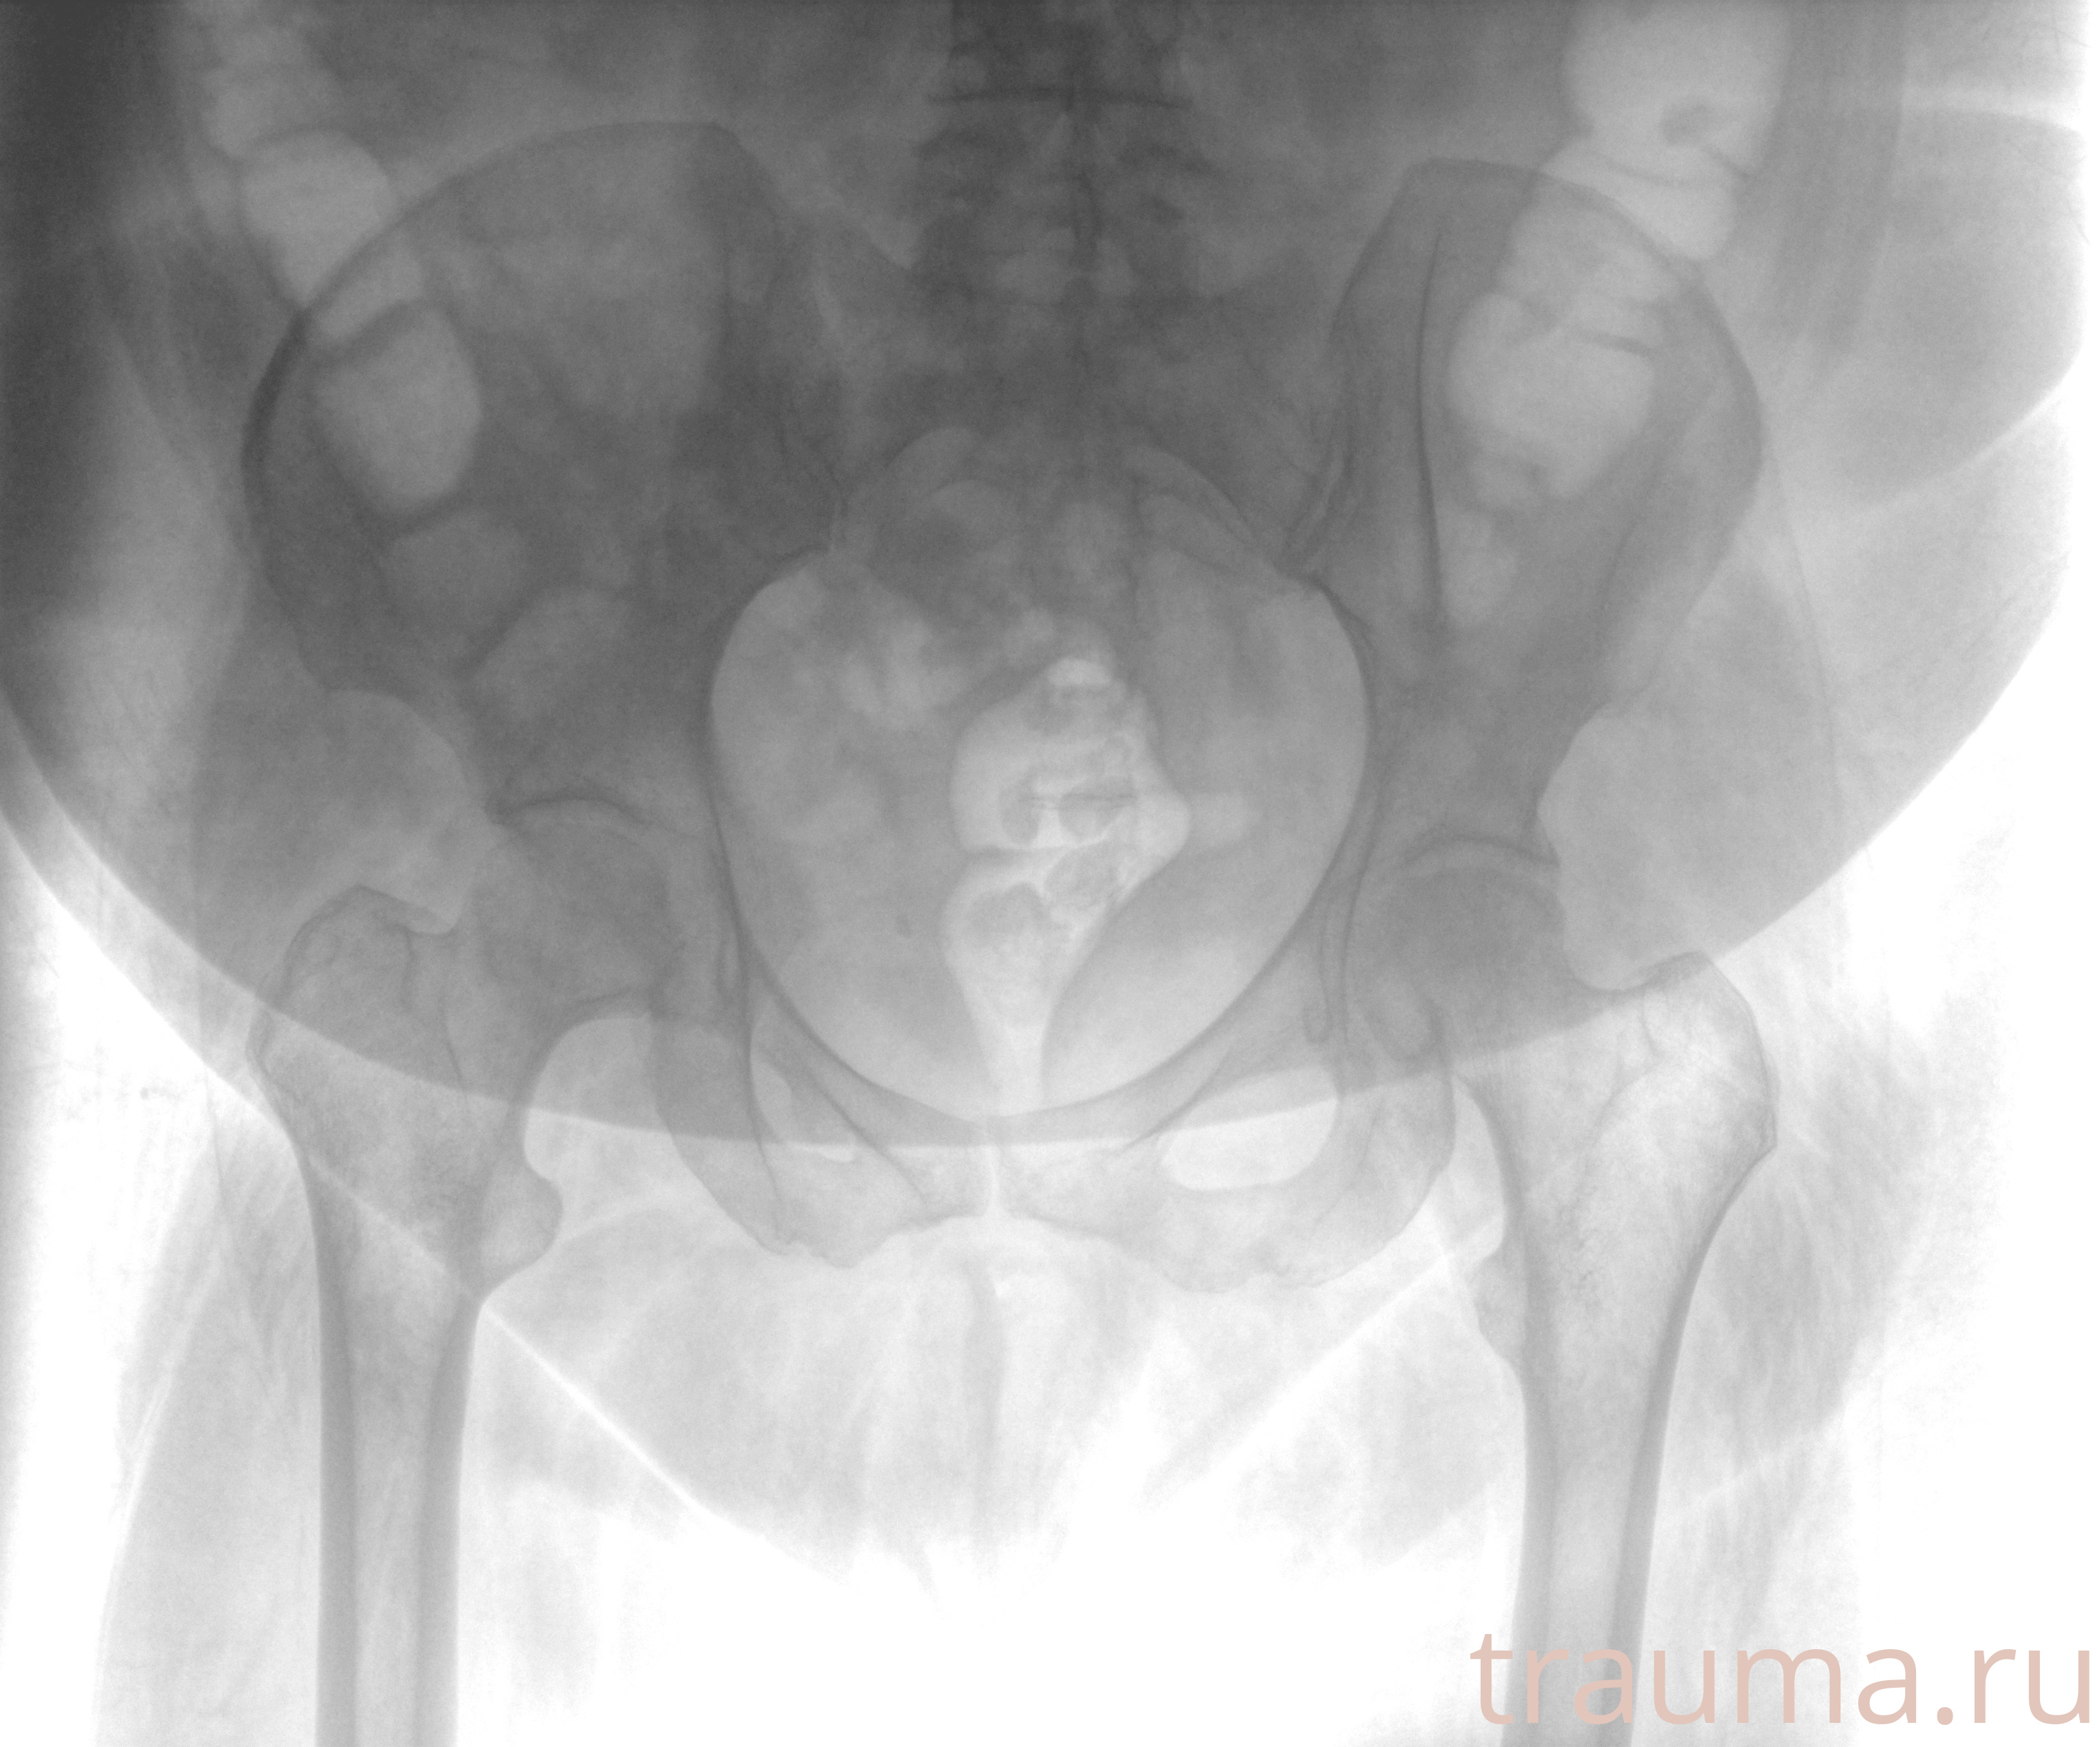

Рентген на дому: по вашему адресу приезжает врач-рентгенолог, травматолог-ортопед с мобильным рентгеновским аппаратом, проводит диагностику травмы или заболевания, делает необходимые рентгенограммы, дает рекомендации по дальнейшему лечению. Получить качественные снимки в домашних условиях возможно благодаря уникальной методике, разработанной МосРентген Центром для института  Склифосовского